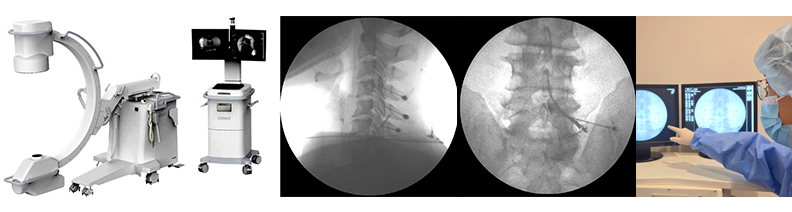

C-arm

C-arm 유도하 척추중재적 시술(C-arm guided intervention)

시술 시간은 10~15분 정도로 짧아 입원이 필요 없으며, 외래에서 간단히 치료할 수 있습니다. 이 치료는 요추간판탈출증, 척추관협착증, 좌골신경통, 척추 후관절증 등 디스크 관련 질환에 매우 효과적입니다. 또한, X-ray 영상을 실시간으로 보여주는 디지털 C-arm 장비를 활용해 이상이 있는 부위에 정확하게 시술하므로 안전하고 효과적인 치료를 제공합니다. 그리고 어깨 관절의 염증과 유착으로 좁아진 오십견도 C-arm을 이용해 좁아진 관절주머니를 넓히고 염증을 가라앉히는 치료제를 주입함으로써, 빠르고 만족스러운 치료 효과를 기대할 수 있습니다.